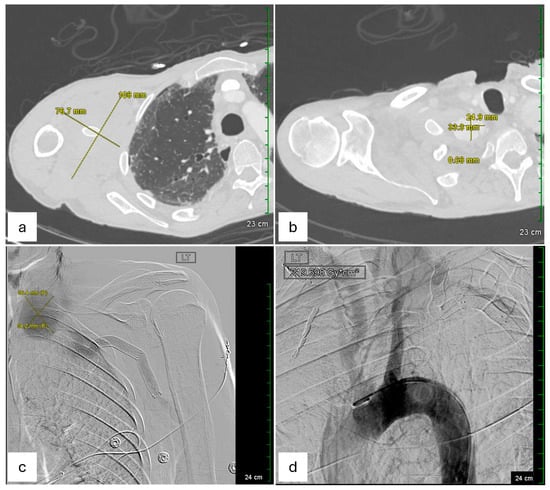

Given the symptomatic presentation and partial rupture of the right subclavian artery aneurysm, an emergent endovascular intervention was performed on the day of admission after obtaining informed consent. The procedure was performed under moderate sedation for 3 h. Vascular access was obtained via ultrasound-guided retrograde right common femoral artery access, and a pigtail catheter was advanced into the proximal ascending aorta for arch and thoracic aorta angiography. Selective catheterization of the right subclavian artery confirmed a large, contained rupture in the mid-subclavian segment, approximately 1 cm distal to the vertebral artery takeoff. Intravascular ultrasound (IVUS) was performed to delineate vessel dimensions and the aneurysm’s relation to the vertebral artery. The intervention involved embolization of multiple collateral branches (right transverse cervical, suprascapular, and internal mammary arteries) using Ruby coils to minimize endoleak risk. Subsequently, an 11 × 59 mm VBX stent (Flagstaff, AZ, USA) was deployed in the mid-subclavian artery with post-stent balloon angioplasty using a 12 × 40 mm balloon. A completion angiogram confirmed successful exclusion of the aneurysm without evidence of endoleak, with brisk antegrade flow into the vertebral artery and upper extremity vasculature. The procedure concluded with percutaneous closure of the right femoral artery using ProGlide Perclose. This procedure succeeded in restoring normal arterial flow and preventing further bleeding. Notably, pre-procedural IR imaging also identified a large left subclavian artery aneurysm, measured to be 56.4 mm * 54.2 mm in dimension, with a contained rupture at its mid-segment, approximately 1.5–2 cm distal to the vertebral artery origin (Figure 2c). The left-sided aneurysm was not well visualized on CTA of the right extremities but was confirmed on angiography.

Figure 2. Pre−procedural imaging studies demonstrate the bilateral subclavian artery aneurysms, their dimensions, and associated vascular pathology. (a) Axial CTA of the right upper extremity demonstrates a large diffuse soft tissue hematoma measuring 76.7 mm * 108 mm, with perivascular soft tissue thickening, without evidence for active extravasation at this time. The aneurysm is located in the mid−subclavian artery, just distal to the vertebral artery takeoff, corresponding to the site of prior stent graft placement. (b) Axial CTA of the right upper extremity reveals irregular morphology of the proximal right subclavian artery measuring 2.5 * 3.3 cm with surrounding thrombus at the right subclavian artery region, measuring 21.9 mm * 33.3 mm, likely indicating partial rupture or pseudoaneurysm. (c) Pre−procedural digital subtraction angiography (DSA) of the left upper extremity from the interventional radiology (IR) suite shows a left subclavian artery aneurysm measuring 56.4 mm * 54.2 mm at its widest diameter. The aneurysm is approximately 1.5−2 cm distal to the vertebral artery takeoff, with evidence of a contained rupture. (d) DSA of the aortic arch and left subclavian artery demonstrates the perfusion of the aneurysm and confirms the location of the pathology before planned intervention on day 1 of hospitalization.